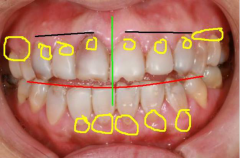

牙齿美学修复是指在不磨牙或少磨牙的情况下,应用粘接材料,将薄层瓷修复体固定于患牙唇、颊面,以恢复影响美观的缺损、遮盖变色等缺陷的一种修复方法。因其较冠类修复备牙少... 详情

牙齿贴面美白牙齿其实就是在牙齿的表面贴上一层贴片,其实美白的原理就是对已经变色的牙齿进行原本颜色的遮挡,这样子就可以达到美白的效果。 天津诺尔牙齿贴面修复的效果 瓷... 详情

瓷贴面是一种很出色的牙齿美容技术,在的美牙方式中,有着独到的优势。瓷贴面不仅可以用来改变牙齿的颜色,而且能够掩饰牙齿部分缺损、牙缝过大等现象,可以说适应症是很广的... 详情

牙齿缝隙大会对个人形象也是很大影响,让人在工作和生活中都失去自信,那门牙缝隙大怎么办?有什么办法可以解决吗?随着口腔技术的发展,限制门牙缝隙大的治疗办法也越来越多,... 详情

牙贴面是一项比较受欢迎的一种牙齿修复方式,能够修复牙齿缺损、牙齿严重变色等问题,深受很多市民朋友的青睐。对于四环素牙、氟斑牙、遗传性黄牙,都可以很有效的帮助牙齿美... 详情